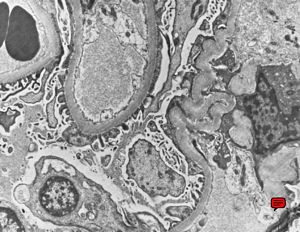

M,67y. | normal kidney

F,49y. | normal kidney

M,34y. | normal kidney

F,2y. | normal kidney